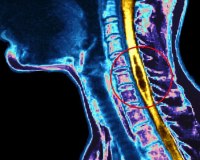

Гидромиелия возникает в основном у детей. Она возникает тогда, когда в верхней части центрального канала спинного мозга наблюдается аномальное расширение. Это приводит к образованию заполненной жидкостью кисты, называемой сиринксом.

Гидромиелия возникает в четвертом желудочке мозга. Это полое пространство находится в нижней части мозга, около ствола мозга. Оно заполнено спинномозговой жидкостью (СМЖ), которая защищает мозг от травм.

Четвертый желудочек соединяется с центральным каналом. Это узкое пространство проходит по всей длине спинного мозга. Центральный канал обеспечивает постоянный приток СМЖ для питания и защиты спинного мозга. Он выстлан особым типом клеток (эпендимальные клетки), которые присутствуют только в желудочках и позвоночном канале.

Когда жидкость накапливается, сиринкс расширяется. Это оказывает давление на спинной мозг, что может привести к раздражению и повреждению нервов.